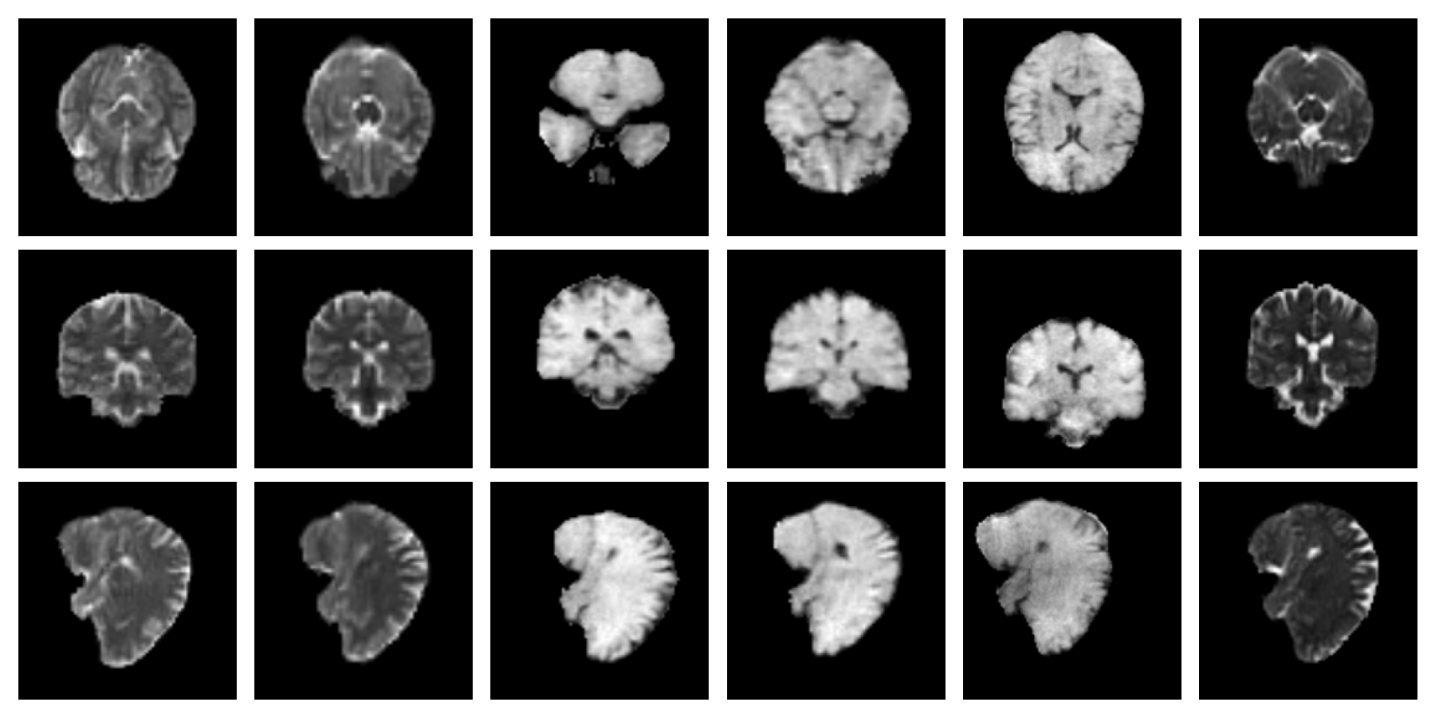

For both the Clinical and Low-field datasets, low-resolution images are skull-stripped and normalized to [-1, 1]. The alignment to MNI space is required by forward model given in Equation 11 and is achieved by recomputing the affine transformation through centroid alignment of anatomical labels from SynthSeg Billot2023 segmentations with the corresponding atlas centroids. Example low-resolution images are shown in Figure 6.

A.8 Additional qualitative restoration results

Additional qualitative results for the Clinical dataset are given in Figures 7, 8 and 9, and for the Low-field dataset in Figures 10 and 11.